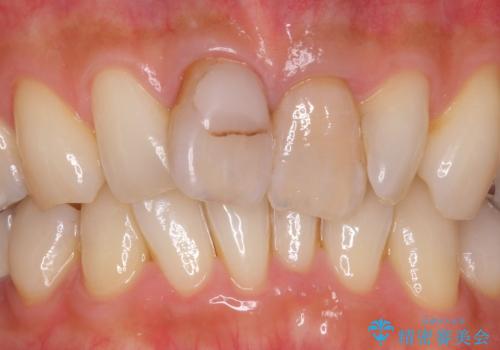

- 前歯の変色とガタつきがきになるとのことで来院されました。

元々根管治療がされていたにも関わらず被せ物が作られておらず、このままではどんどん変色が進んでいってしまう状態でした。

歯をある程度削ることにはなりますが、被せ物にすることで歯の変色を隠し短期間でキレイな口元に仕上げることができました。

前歯の色・形・ガタつきともに改善することができ、大変喜んでいただけました。